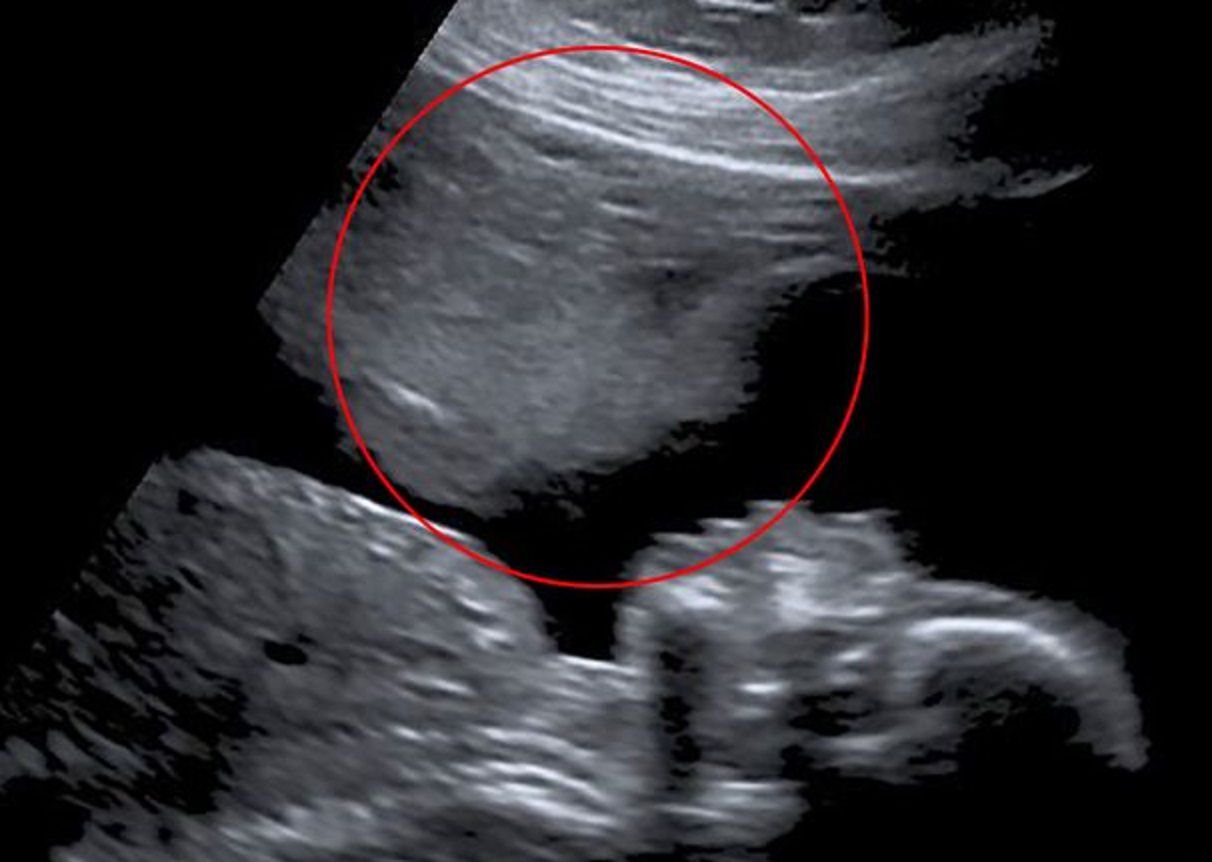

Natomiast to badania w 20. tygodniu zapadły Stacey najbardziej w pamięć. Na ekranie ultrasonografu tuż nad twarzą jej dziecka, pojawiła się druga, przypominająca ducha. Zdaniem kobiety był to "anioł stróż", który chronił jej syna przed komplikacjami.

"Myślę, że może być tam coś (lub ktoś) kto tym razem troszczy się o nas – mówi. – Nie przestałam się martwić, ale odetchnęłam z ulgą" - wspomina.